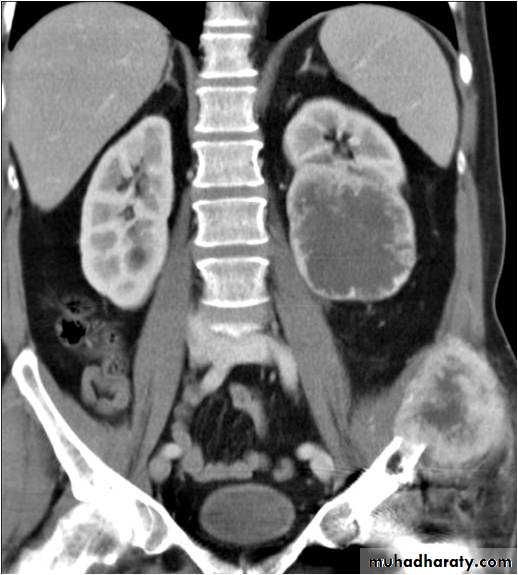

Ct enhanced

Big simple renal cyst(non enhancing mass homogenous) treatment is conservative or drainge if symptomaticWhat's the Diagnosis?